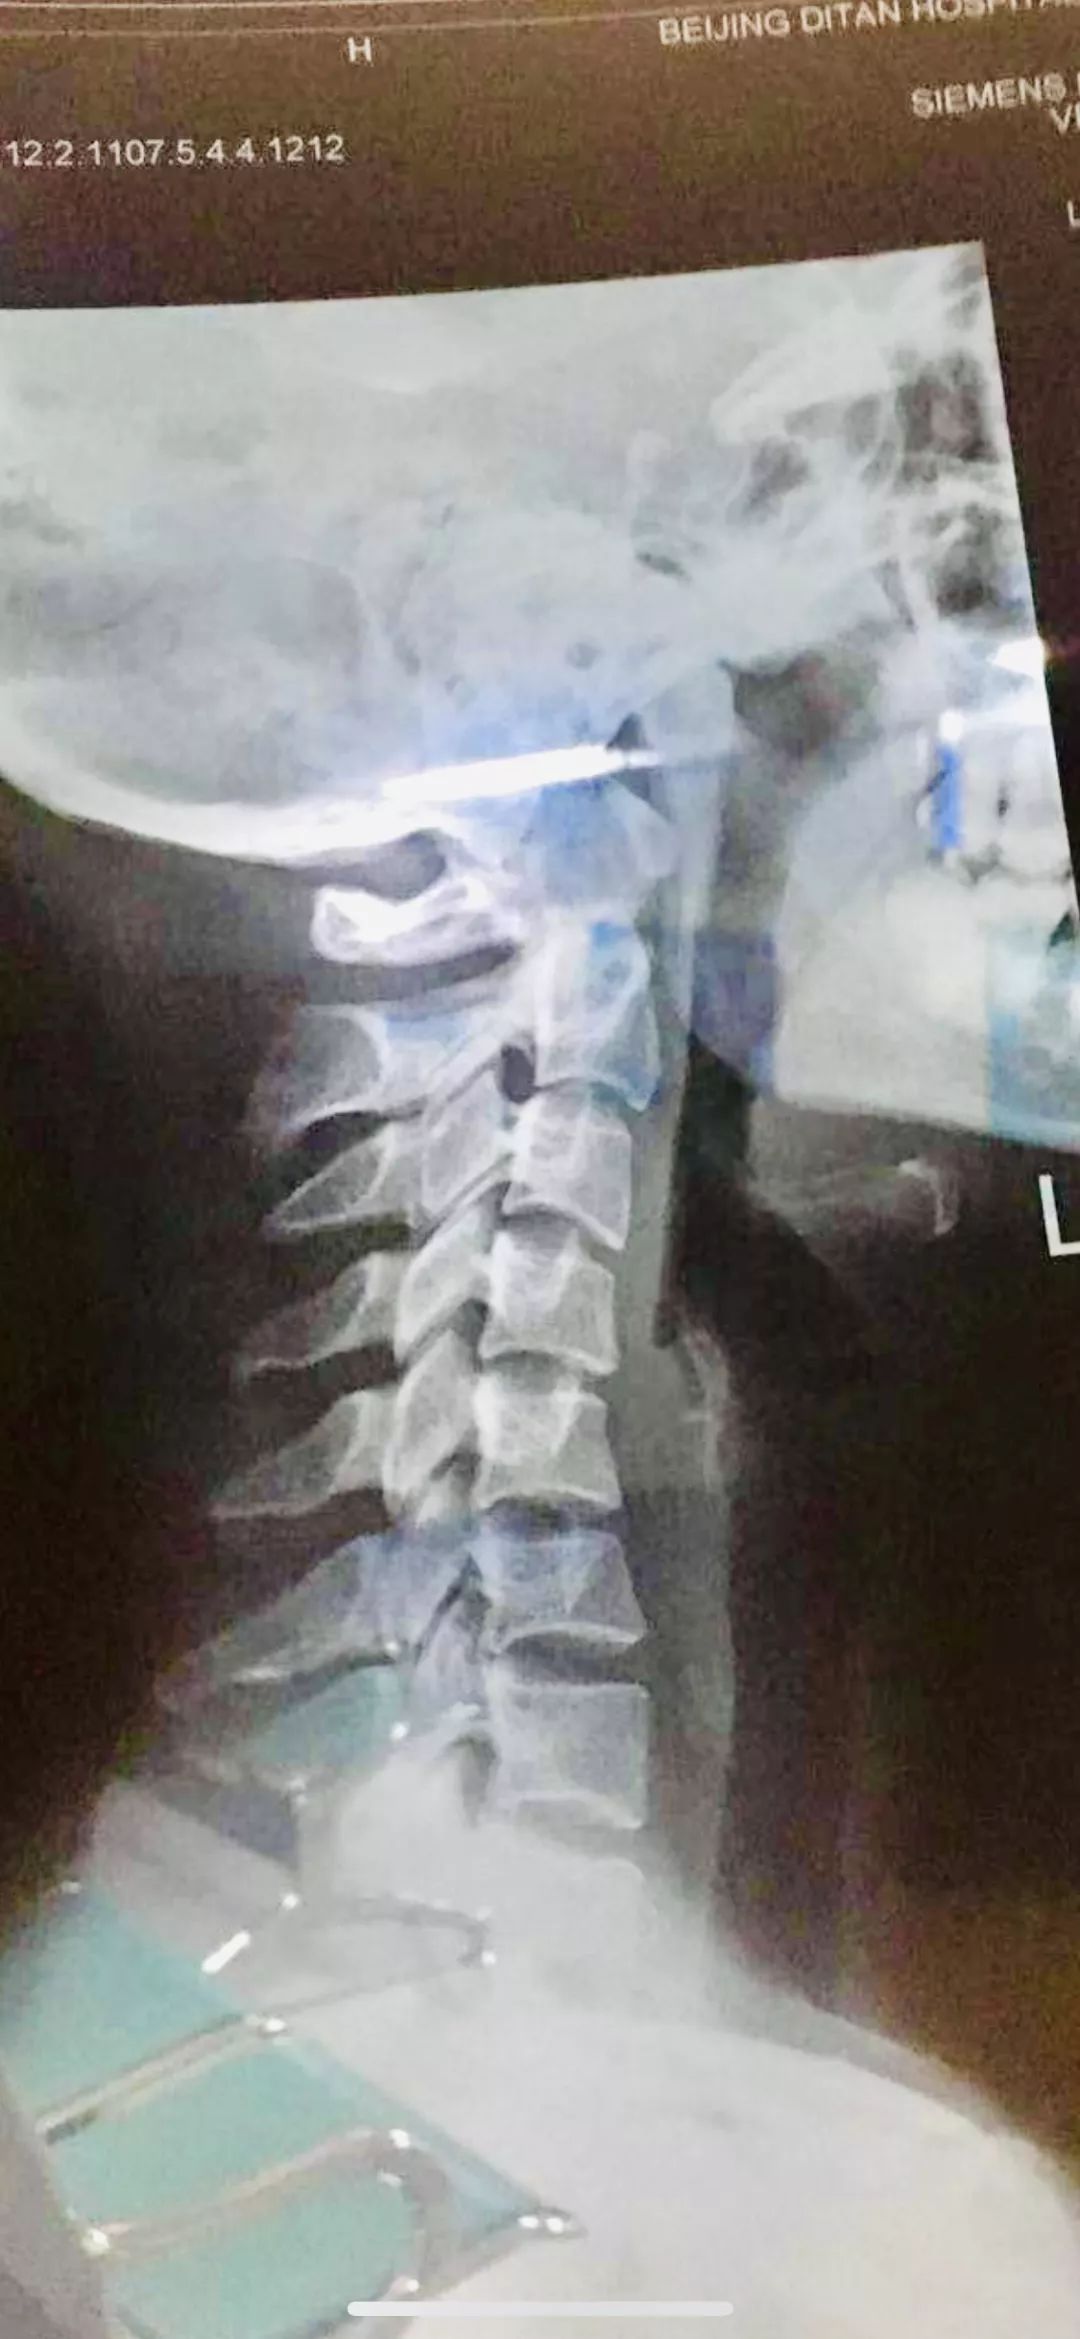

最近,家住长沙市开福区的王女士每天都觉得脖子和肩膀很酸,像是背着几千斤东西一样,特别容易犯困,头晕,恶心,头痛,有时甚至无法工作,只能卧床休息。王女士到我院就诊,推拿科副主任李鑫接诊并了解到她长期低头玩手机,上班也是长时间对着电脑。经过仔细查体及触诊,发现她的椎体发生了移位,拍片检查结果显示:颈椎反弓了。经李鑫针灸、推拿治疗后,王女士感觉好多了。

颈椎反弓是一种常见的颈椎病,正常的颈椎呈现C形的生理弧线,既保证了颈椎的活动度,也能缓冲力量,如果这种生理曲度一旦消失,甚至出现向相反的方向弯曲,就称为颈椎反弓。一旦颈椎的动脉受压,就会出现大脑供血不足,颈项部肌肉和韧带受牵拉,就会出现颈部肌肉酸痛等。

如果您“颈椎反弓”了,不要着急,我院针灸推拿康复中心为您保驾护航,推拿手法一方面可以放松患者颈项部的肌肉,另一方面通过触诊并结合患者颈椎X线片定位,确定偏歪的颈椎,用整脊手法使偏歪的椎体位置得到纠正,减轻神经根或血管的压迫和刺激,恢复颈椎内外环境的稳定。针灸可以选择夹脊穴、阿是穴等疏通经络。另外还可以选择中药热敷等放松肌肉。